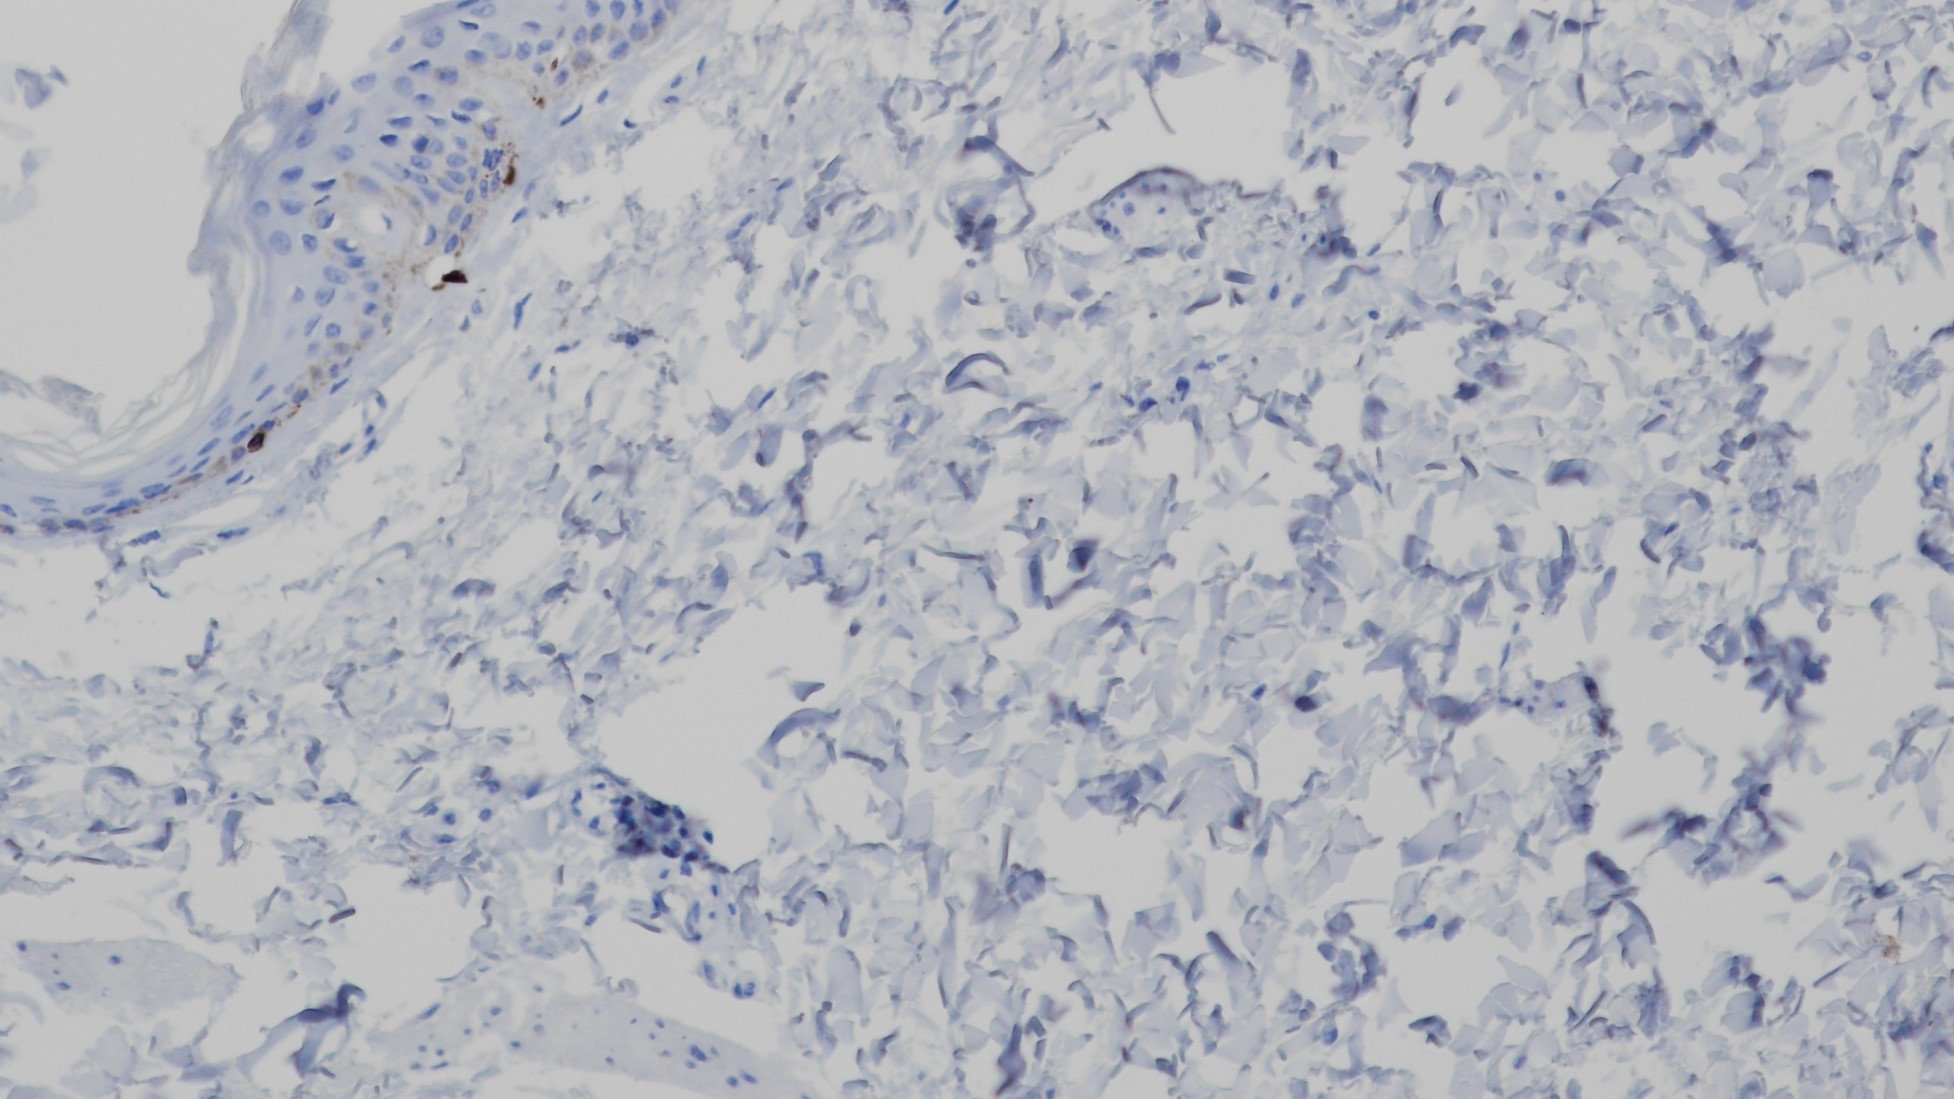

1. Kapur RP, et al. Anti-melanoma monoclonal antibody HMB45 identifies an oncofetal glycoconjugate associated with immature melanosomes. J Histochem Cytochem. 1992 Feb; 40(2):207-12.